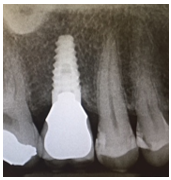

Following periodontal re-evaluation confirming gingival health and adequate patient compliance, the extraction of 16 with alveolar ridge preservation was scheduled. The roots of the 16 were sectioned and removed. The socket was preserved using a xenograft. Careful elevation of the facial and palatal mucosa was performed in order to create a pouch that would stabilise a collagen membrane. After 20 weeks of healing, the gingiva was of mature aspect with no signs of infection. The patient returned for planned surgical placement of a suitable 4.6 × 10.5mm BioHorizons Tapered Internal dental implant with a Laser-Lok collar, and the assistance of a fabricated restorative-driven surgical template for surgical placing. In view of the adequate amount of keratinised mucosa and excellent primary stability, a non-submerged surgical approach was selected (Figure 1 and 2).

From Left to right; 1. Radiograph of placed implant with healing abutment. 2. Photograph of healed gingiva 10-weeks post-op. 3. Radiograph 1-year post-op. 4. Photograph 1-year post op of restored implant.